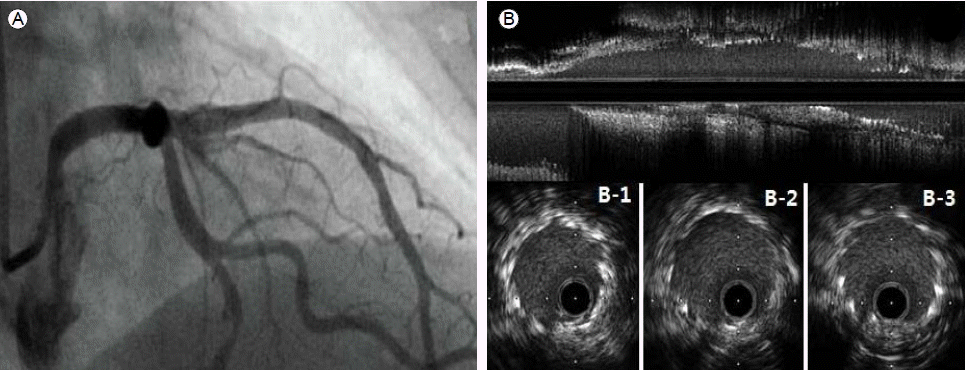

Figure 1.

On pre-intervention angiography, (A) the left anterior oblique cranial view shows stenotic lesions in the proximal and middle left anterior descending artery, and (B) the right anterior oblique cranial view shows a significant stenotic lesion (arrows).

74세 여자가 1개월 전부터 발생한 흉통을 주소로 본원에 내원하였다. 환자는 제2형 당뇨병을 진단받고 투약 중이었으며 그밖에 특이 병력, 과거력 및 가족력은 없었다. 심전도와 심초음파에서는 이상소견이 없었으나 심근 관류 단일 광자 방출 전산화 단층 촬영(single photon emission computed tomography, SPECT)에서는 좌전하행지 영역에 가역적인 병변이 있음을 확인하였다. 이후 시행한 관상동맥 조영술에서 좌전하행지의 근위부와 중간부에서 심한 협착 소견을 확인할 수 있었다(Fig. 1). 일차적으로 풍선 확장술을 시행하였고 3.5 × 15 mm, 2.75 × 14 mm zotarolimus 방출 스텐트(Endeavor resolute, Medtronic, Minneapolis, USA)를 좌전하행지의 근위부와 중간부에 각각, 중복(overlapping) 없이 12기압으로 확장하여 삽입하였다. 이후 관상동맥 조영술에서 최적의 결과를 얻었으며(Fig. 2A) 삽입된 스텐트를 평가하기 위해 혈관 내 초음파(intravascular ultrasound, IVUS)를 시행하였다. 혈관 내 초음파 카테터(Atlantis SR Pro, Boston Scientific Corporation, Boston, USA)를 좌전하행지의 원위부에 위치시킨 후 자동 후퇴를 하면서 영상을 얻었다. 그 결과 스텐트는 관상동맥 내에 적절하게 삽입되어 있었고, 불완전 확장(underexpansion) 소견은 관찰되지 않았다(Fig. 2B, 2B-1~2B-3). 이후 혈관 내 초음파를 수동으로 당겨내던 중 카테터의 끝부분(tip of IVUS)이 근위부의 스텐트 위치에 다다랐을 때 저항이 느껴졌다. 저자들은 일단 가이딩 카테터 및 유도철선, 초음파 카테터를 한꺼번에 조심스럽게 당겼으나 결국 초음파 카테터는 제거할 수 없었다. 그래서 일단 혈관내 초음파 카테터의 유연성을 높이기 위해 탐촉자(transducer)와 그것을 둘러싸고 있는 집(sheath)을 분리하고 탐촉자를 먼저 제거한 뒤 카테터 집을 당겼다. 이후 제거된 카테터 집의 끝(sheath tip of guidewire exit port)이 찢어진 걸 확인할 수 있었으며(Fig. 2C) 직후 시행한 조영술에서 근위부 스텐트 부분에 이전 조영에서는 보이지 않던 흐릿한 영상(haziness)을 관찰할 수 있었다(Fig. 2D). 이를 면밀히 관찰하고자 새로운 가이딩 카테터, 유도철선을 적절히 위치시킨 뒤 혈관 내 초음파를 시행하였으며 스텐트 내 스텐트 현상(stent in stent appearance; 스텐트의 완전 골절 이후 골절된 스텐트의 원위부가 근위부로 중첩되어 들어가는 현상, Fig. 2E-1), 스텐트 골절(stent fracture, Fig. 2E-2) 그리고 불완전 스텐트 부착(incomplete stent apposition, Fig. 2E-3)의 발생을 확인할 수 있었다. 이를 해결하기 위해 3.5 mm 크기의 풍선을 이용해 혈관 확장술을 시행한 뒤 4.0 × 24 mm zotarolimus 방출 스텐트(Endeavor resolute, Medtronic, Minneapolis, USA)를 이전 삽입한 근위부 스텐트에 중복하여 좌주간지 입구까지 삽입하였다. 이후 확인한 혈관 내 초음파에서는 스텐트가 혈관벽에 잘 부착되어 있음을 확인할 수 있었으며 조영술에서도 스텐트 변형은 더 이상 관찰할 수 없었다(Fig. 3). 환자는 다른 합병증 없이 퇴원하였으며 9개월 후 추적 관상동맥 조영술 및 혈관 내 초음파에서 스텐트가 잘 보존되어 있음을 확인할 수 있었다.